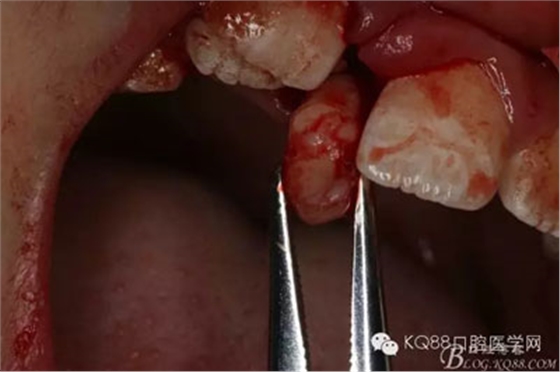

圖11.多生牙呼之欲出

圖12.持針器取出多生牙

圖13.僅作11與21之間的齦乳頭縫合。簡單明了,手術(shù)完成。

該病例首先通過CBCT術(shù)前的精準(zhǔn)定位、從而確定手術(shù)進(jìn)路,然后采用小切口、小翻瓣,達(dá)到暴露多生牙、運(yùn)用微創(chuàng)牙挺和持針器就能順利完成埋伏多生牙的拔除。特別適合兒童多生牙的拔除。